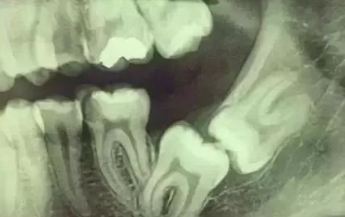

先放张图,让你们涨涨姿势,不拍片根本不知道你的牙齿长得会有多奇葩!

牙齿的牙根是埋在牙槽骨中的,医生没有透视眼,为了解患牙的牙根的形态、走向、长度及根尖周有无病变及病变大小,或者怀疑有肉眼无法确认的其它牙科问题,都会建议患者去牙科的X光,甚至,口腔CT来全面性地确认问题,以订定合适的治疗计划。